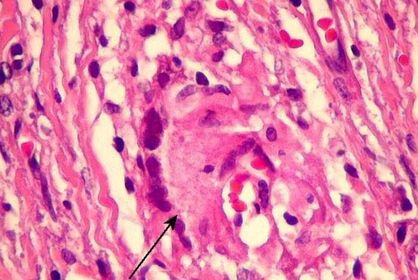

Diagnóstico e alterações PÊNFIGO VULGAR Clivagem Acantolítica Suprabasal